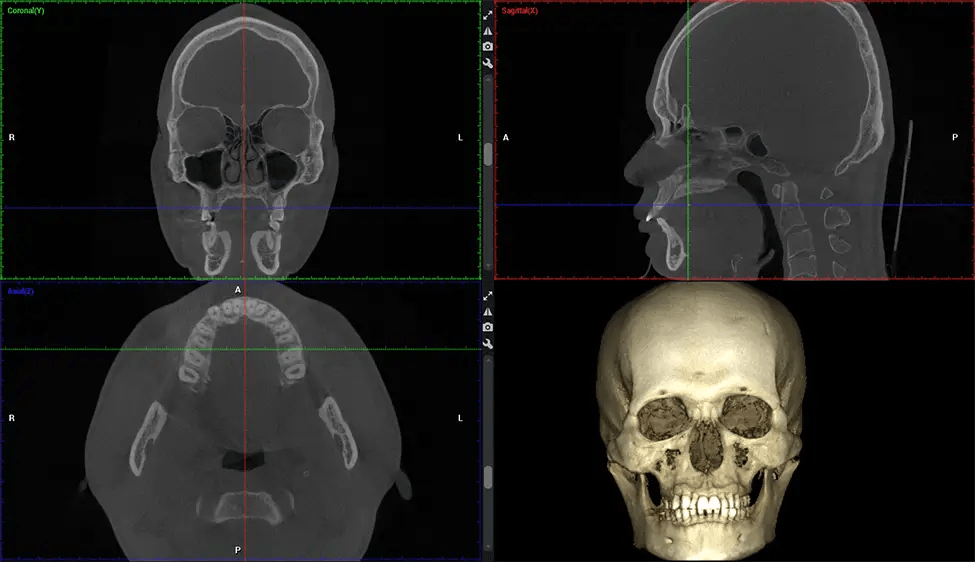

There are many benefits to using CBCT technology, especially compared to the traditional 2D X-ray format. One of the most significant advantages of CBCT scans is that they provide much more information than traditional X-rays. A scan lets your dentist see images from all angles of your jaw and mouth, including your sinuses, nasal cavity, cheekbones, and other surrounding areas. This added information helps your dentist craft a comprehensive treatment plan that addresses all aspects of your oral health.

Planmeca Viso G7 CBCT ( Cone Beam CT Scan ) is designed to surpass the demands of industry leaders, specialists, and large institutions. It’s has a large ø25×30 cm sensor with four built-in cameras. It can capture unlimited volume sizes from a ø3×3 cm to a ø30x30cm volume capturing the skullcap through C7 on the cervical spine. The Planmeca Viso G7 offers the industry’s largest single volume scan of ø30×19 cm. It’s poised to handle advanced imaging modalities such as Planmeca ProFace® and Planmeca 4D™ Jaw Motion technology. The occipital head support allows an unimpeded view of facial tissue.